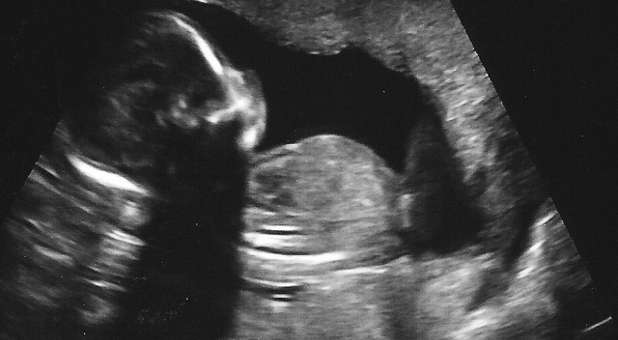

The law that goes into effect on July 1 prohibits the use of dilation and evacuation. The bill says the procedure can result in the fetus being extracted in pieces.

Supporters in Kansas have called the procedure horrifying while women’s healthcare groups have said it is considered the safest way to terminate a pregnancy in the second trimester.

The law allows for the procedure to preserve the life of a pregnant woman or when the mother’s health is in serious jeopardy from the pregnancy.